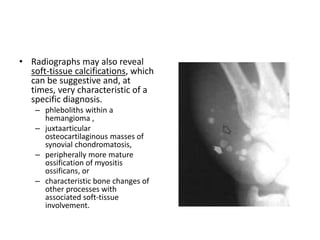

• Radiographs may also reveal

soft-tissue calcifications, which

can be suggestive and, at

times, very characteristic of a

specific diagnosis.

– phleboliths within a

hemangioma ,

– juxtaarticular

osteocartilaginous masses of

synovial chondromatosis,

– peripherally more mature

ossification of myositis

ossificans, or

– characteristic bone changes of

other processes with

associated soft-tissue

involvement.